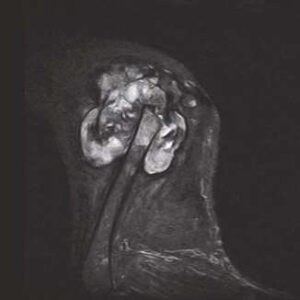

The PANION PRO comes with the double-pole open magnet design with a wide opening gap of 40 cm to accommodate large-sized animals on an efficient patient handling platform, the strongest gradient amplitude at 33mT/m and slew rate of 90 T/m/s, among all other open MRI systems, resulting in high spatial resolution of images in short scan time. The 6-direction patient table permits iso-centre imaging of all anatomical regions.

Clinical Images